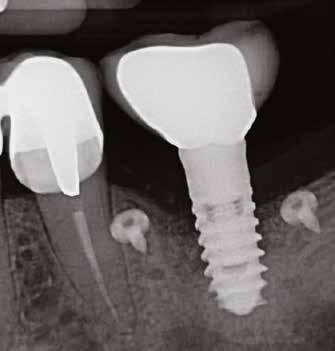

lási csavarokat (PEEK titáncsavarral) maximum 15 Ncm-rel húztuk meg (3–6. ábra). Az összes implantátum kiváló stabilitást mutatott (a mérésekhez Periotestet használtunk, a Medizintechnik Gulden jóvoltából), és teljesen osszeointegrálódott. Ezt a radiológiai vizsgálatok is megerősítették.

3. a–b ábra: Röntgenfelvételek három hónap után (a) és a gyógyulási csavarok behelyezve (b, 1. eset).